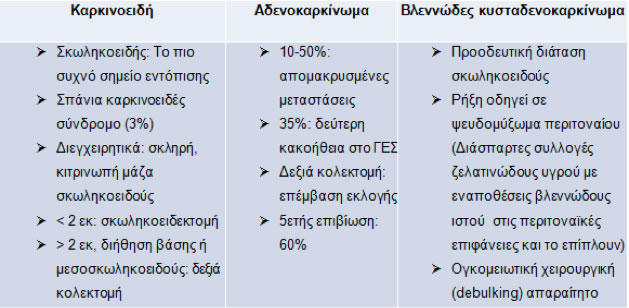

Επίπτωση κακοήθων όγκων (καρκινοειδή, αδενοκαρκινώματα, κακοήθης βλεννοκήλη ή βλεννώδες κυσταδενοκαρκίνωμα): 1,4% παρασκευασμάτων σκωληκοειδεκτομής (Πίνακας 6).

Κλινική εικόνα:

- Διάγνωση σχεδόν ποτέ προεγχειρητικά.

- Κλινικές εκδηλώσεις οξείας σκωληκοειδίτιδας, καρκινοειδές σύνδρομο, ψηλαφητή κοιλιακή μάζα, ασκίτης σε βλεννοπαραγωγά νεοπλάσματα.

Πίνακας 6.

Βασικά χαρακτηριστικά και θεραπευτική αντιμετώπιση κακοήθων νεοπλασμάτων σκωληκοειδούς